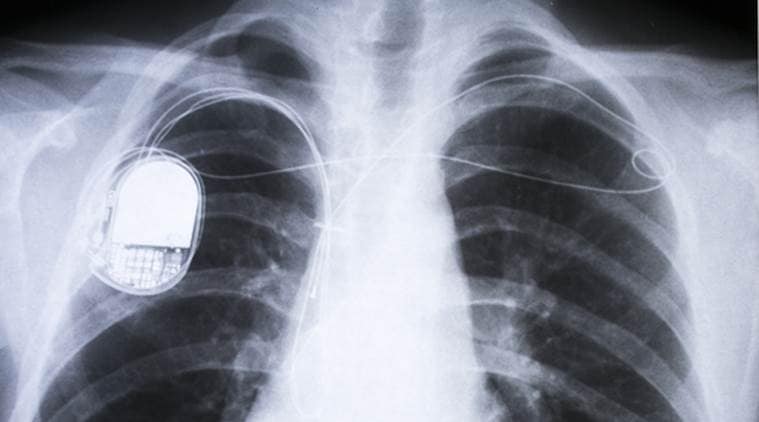

Energy, Universe, Technology, Medical devices, Artificial cardiac pacemaker, Biomedical engineering, Cardiac electrophysiology, Cybernetics, Neuroprosthetics, Heart, PAVE, Solar cell, Proceedings of the National Academy of Sciences Unlike today’s pacemakers, this method appears to ‘train’ the cardiac muscle to beat. (Representational Image: Thinkstock)

Scientists have developed a tiny solar cell that encourages the heart to beat, an advance that may pave the way for pacemakers powered by light. Researchers from the University of Chicago in the US created a flexible mesh out of silicon, that when activated by flashes of light, creates a tiny electrochemical effect which can stimulate the heart muscle in a unique way.